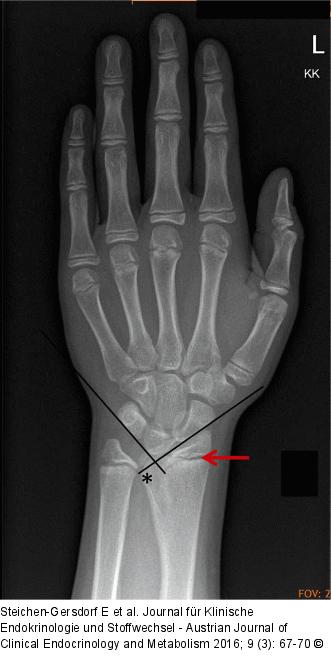

Abbildung 2: Radiologische Zeichen Radiologische Zeichen der SHOX-Defizienz, Knochenalter 13 Jahre a) Fusion der ulnaren Radiusepiphyse (Triangulation), siehe Pfeil b) Aufhellung der distalen Radiusmetaphyse (Radiolucency), * c) spitzer Karpalwinkel (Pyramidalisation der proximalen karpalen Reihe) |

Radiologische Zeichen der SHOX-Defizienz, Knochenalter 13 Jahre a) Fusion der ulnaren Radiusepiphyse (Triangulation), siehe Pfeil b) Aufhellung der distalen Radiusmetaphyse (Radiolucency), * c) spitzer Karpalwinkel (Pyramidalisation der proximalen karpalen Reihe) |